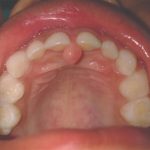

The elevation of soft tissue covering the foramen of the incisive or nasopalatine canal.

A small bump in the mucosa above and just to the front of the incisive foramen at the very front of the hard palate. The papilla is used as an injection site when anesthetizing the nasopalatine nerve.